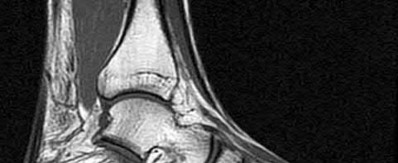

2. # A 35-year-old woman is involved in a head-on collision while driving. Initial radiographs are shown in Figures 8a and 8b. Injury to what vessel increases the risk for osteonecrosis of the injured bone?

5. Artery of the tarsal sinus Corrent answer: 4

The patient has a Hawkins type III talar neck fracture-dislocation with a risk of osteonecrosis ranging from 69% to 100%. Anatomic studies have shown that the artery of the tarsal canal supplies the lateral two thirds of the talar body.

The other vessels listed provide no significant contribution to the talus.